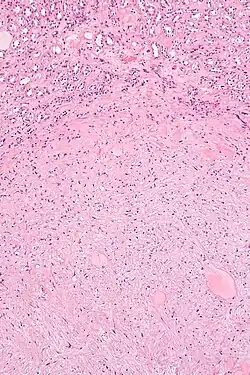

| Micrograph of a renal medullary fibroma (bottom of image). Renal tubules are seen at the top of the image. H&E stain. | |

They consist of bland spindle-shaped or stellate-shaped cells in a loose stroma. Renal tubules may be entrapped.